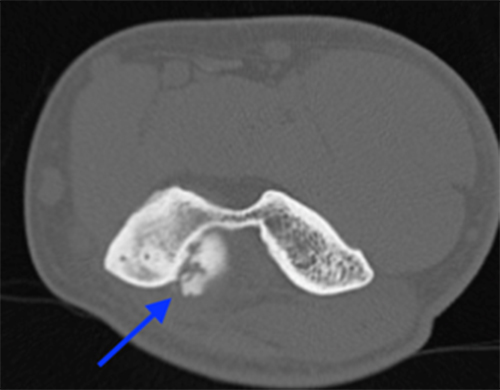

- CT scan is best for identifying loose bodies and osteophytes for surgical planning

CT scan demonstrates posteromedial osteophytes within the olecranon fossa